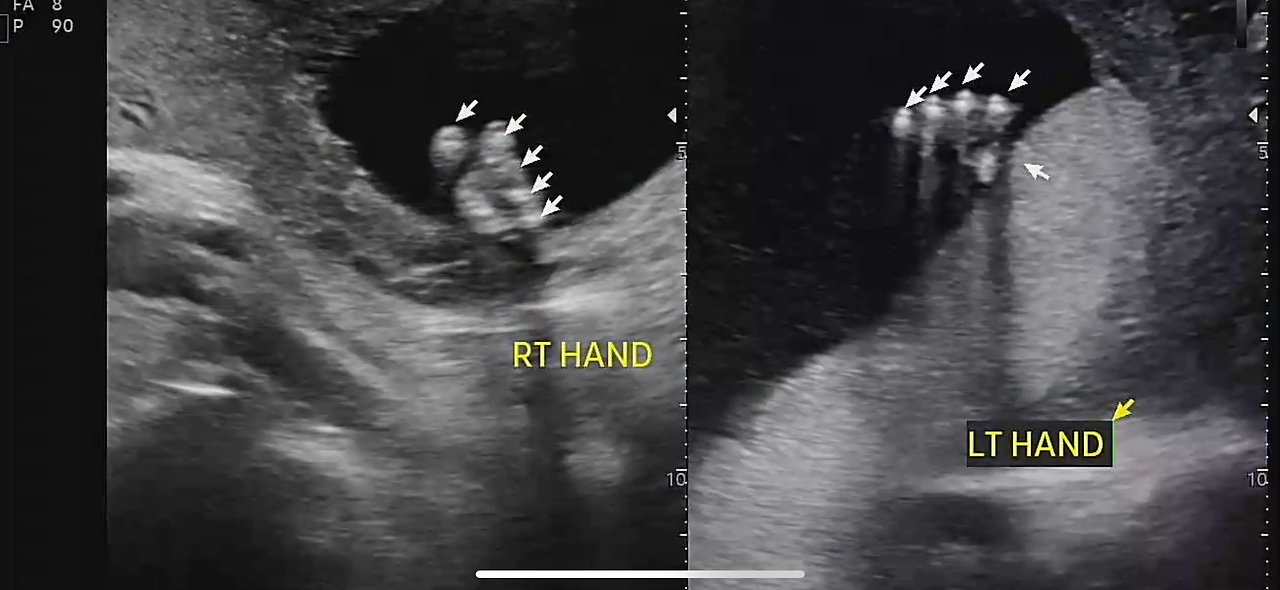

정밀 초음파는 생각보다 오래 걸렸다.

30분 가까이 이어진 검사 동안

손가락, 발가락, 귀, 콧구멍까지

아이는 하나하나 자세히 확인되었다.

22주 정밀초음파